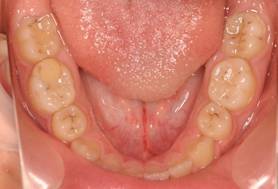

インビザGOによる矯正症例1 16歳男性

マウスピース矯正開始前。右上犬歯が内側にありました

4か月後。犬歯が外側に出てきました